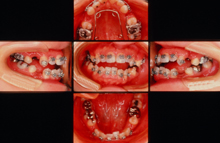

・CASE 4 ~ 受け口 ~

治療前 12歳2ヶ月

治療後 13歳8ヶ月

治療後 10年後 23歳6ヶ月

CASE 4 ~受け口~ 永久歯が生えるスペースがない、上下の歯が反対咬合でよく噛めない。

治療前(初診時年齢)12歳2ヶ月の女児

物が噛みきれない

マルチブラケット装置(表側ワイヤー装着)上下左右第一小臼歯を抜歯して治療しました

治療後 13歳8ヶ月 治療期間1年6ヶ月 治療費700,000円

副作用とリスク(一時的な顎関節の痛み、歯の痛み、歯が磨きにくい、口内炎、しゃべりづらい、歯根吸収、歯肉退縮、後戻り、治療期間について説明しました。)

保定終了後 6年10ヶ月 22歳1ヶ月